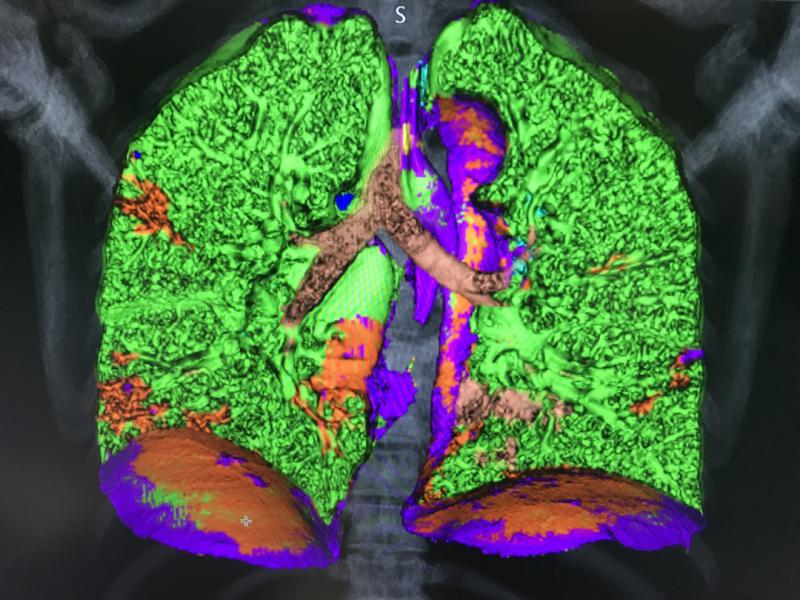

This photo gallery shows the variety of radiological presentations of COVID-19 (SARS-CoV-2) in medical imaging, including computed tomography (CT), radiograph X-rays, ultrasound, echocardiograms and magnetic resonance imaging (MRI). The radiology images show examples of typical COVID pneumonia in the lungs and the numerous complications the virus causes in the body in multiple organs, including the brain, kidneys, heart, abdomen and vascular system.